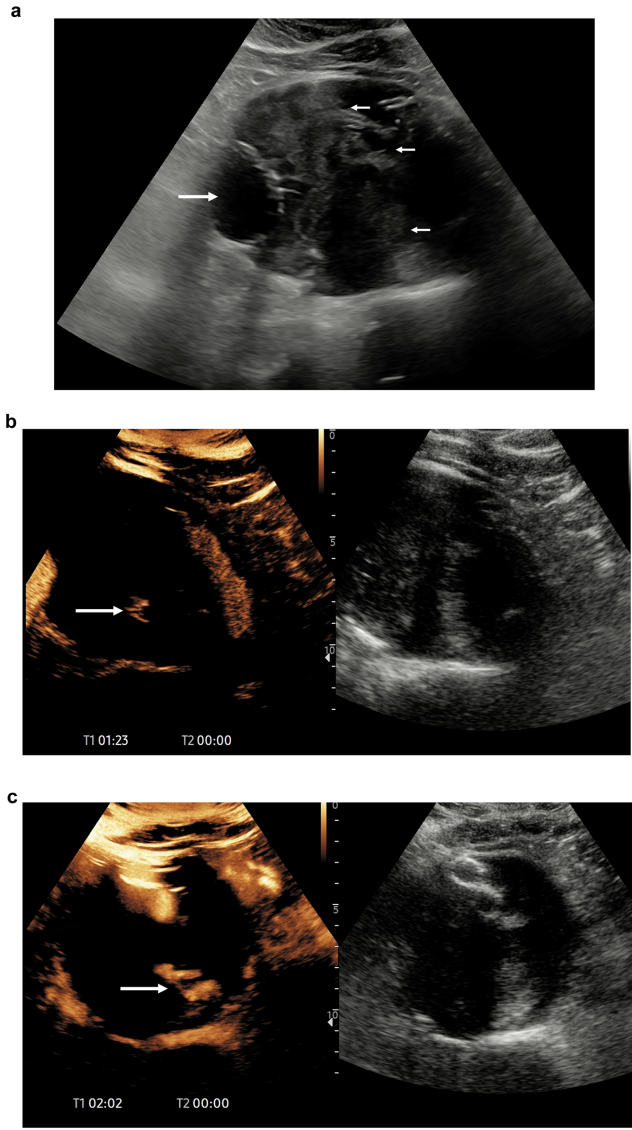

数据显示微泡造影剂无法穿透胎盘屏障,妊娠期CEUS诊断肝脓肿、胎盘植入时胎儿均无显影。相比存在钆沉积风险的MRI,CEUS在29岁孕妇肝脓肿案例中精准显示病灶周边强化,而妊娠囊始终保持无增强状态

FDA已批准LumasonTM用于儿童肝病变诊断。14岁自身免疫性肝炎患儿通过CEUS明确12mm病灶为良性局灶性结节增生(FNH),动脉期"轮辐状"强化模式清晰可见

CEUS对实质器官损伤的敏感性达93.3%(CT为95.6%),39岁摩托车事故患者脾脏假性动脉瘤在CEUS下无所遁形

CEUS检出>2mm分隔的灵敏度超CT,78岁患者18mm肾囊肿经CEUS升级为Bosniak IIF类

CEUS对II型内漏的检出率等同CT,81岁患者支架术后3年囊腔扩张仅CEUS捕捉到腰动脉返流